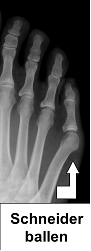

Vor einer Operation wird eine Röntgenaufnahme unter Belastung des Vorfußes erstellt. Anhand der Bildgebung beurteilt der Arzt die Große des Mittelfußköpfchens des fünften Zehs. Zudem misst er den Winkel zwischen den Mittelfußknochen der vierten und fünften Zehe (Intermetatarsale-IV/V-Winkel), der normal etwa 8 Grad beträgt und den Winkel zwischen der fünften Zehe und dem Mittelfuß (normal 5 Grad). Die operative Therapie stützt sich auf diese Befunde.